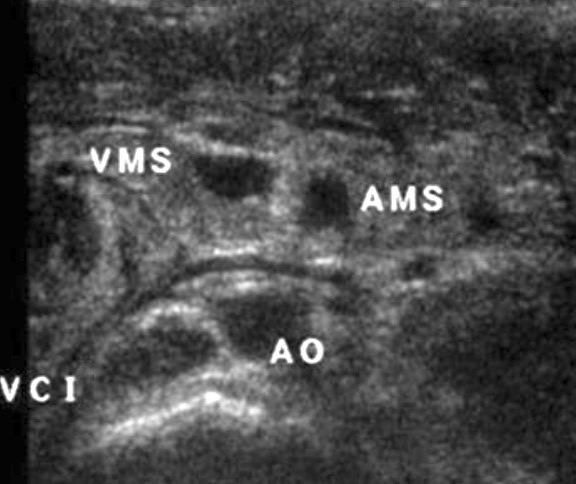

- vomis bilieux NNé < S2 à ventre plat, 80% < 1 an mais peut survenir à tout âge

- complique une mésentère commun incomplet (malrotation intestinale)

signe du tourbillon => PEC chirurgicale immédiate

signe du tourbillon => PEC chirurgicale immédiate

écho non contributive / négative => opacification digestive haute

écho non contributive / négative => opacification digestive haute